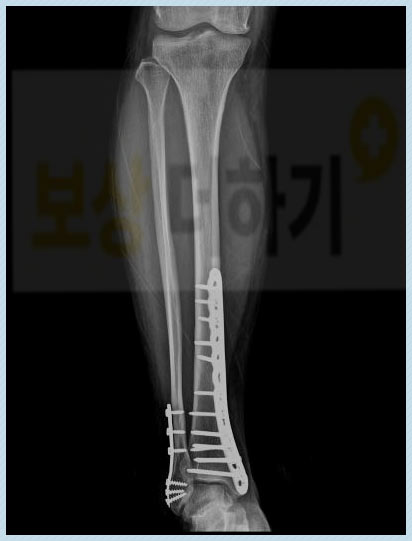

진단명: 비골 골절(모든 부분)을 동반한 경골 하단의 골절 S82320 엑스레이 사진을 보면 다리에 두 개의 긴 뼈가 보이죠? 굵은 뼈가 경골, 상대적으로 가는 뼈가 비골입니다. 이번 사고로 경골과 비골의 하단이 골절된 것 즉 복숭아뼈(양 복사뼈)가 골절된 것입니다. 경비골 골절, 양과 골절이라고 합니다.

작은 부상이 아닌만큼 깁스 등 보존적 치료로는 뼈의 유합이 어려운 상태였어요. 따라서 금속판 내고정술을 시행하고 석고 깁스를 하면서 몇 개월간 안정을 취해야 했습니다.